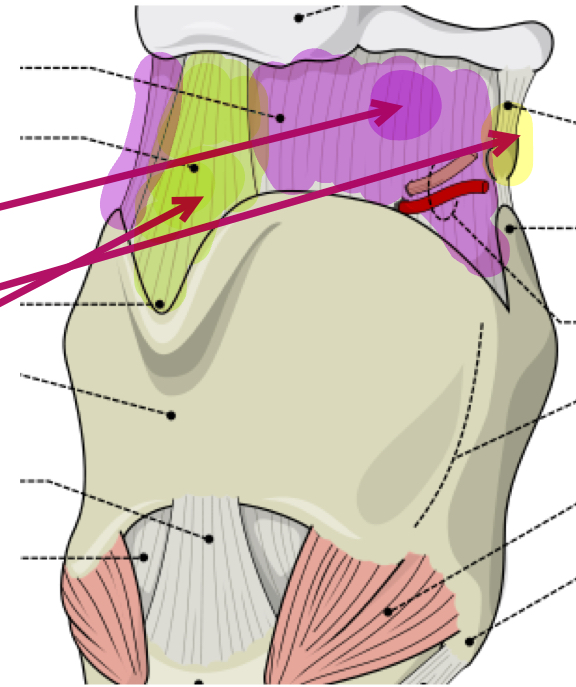

What is the purple membrane?

Thyrohyoid membrane

What is the green ligament?

Middle thyrohyoid ligament

What is the yellow ligament?

Lateral thyrohyoid ligament

What is this muscle?

Lateral cricoarytenoid (LCA) (adduct VF)

What is this muscle?

Transverse arytenoid (adduct VF)

What is this muscle?

Oblique arytenoid (pull apex medially, assist in adducting VF)

What is this muscle?

Posterior cricoarytenoid (PCA) (rocks arytenoid out, abduct VF)

What is this muscle?

Cricothyroid (rocks thyroid forward, pitch up)

What is this muscle?

Thyrovocalis (tense VF, pitch up)

What is this muscle in purple?

Thyromuscularis (VF relaxer, pitch down)